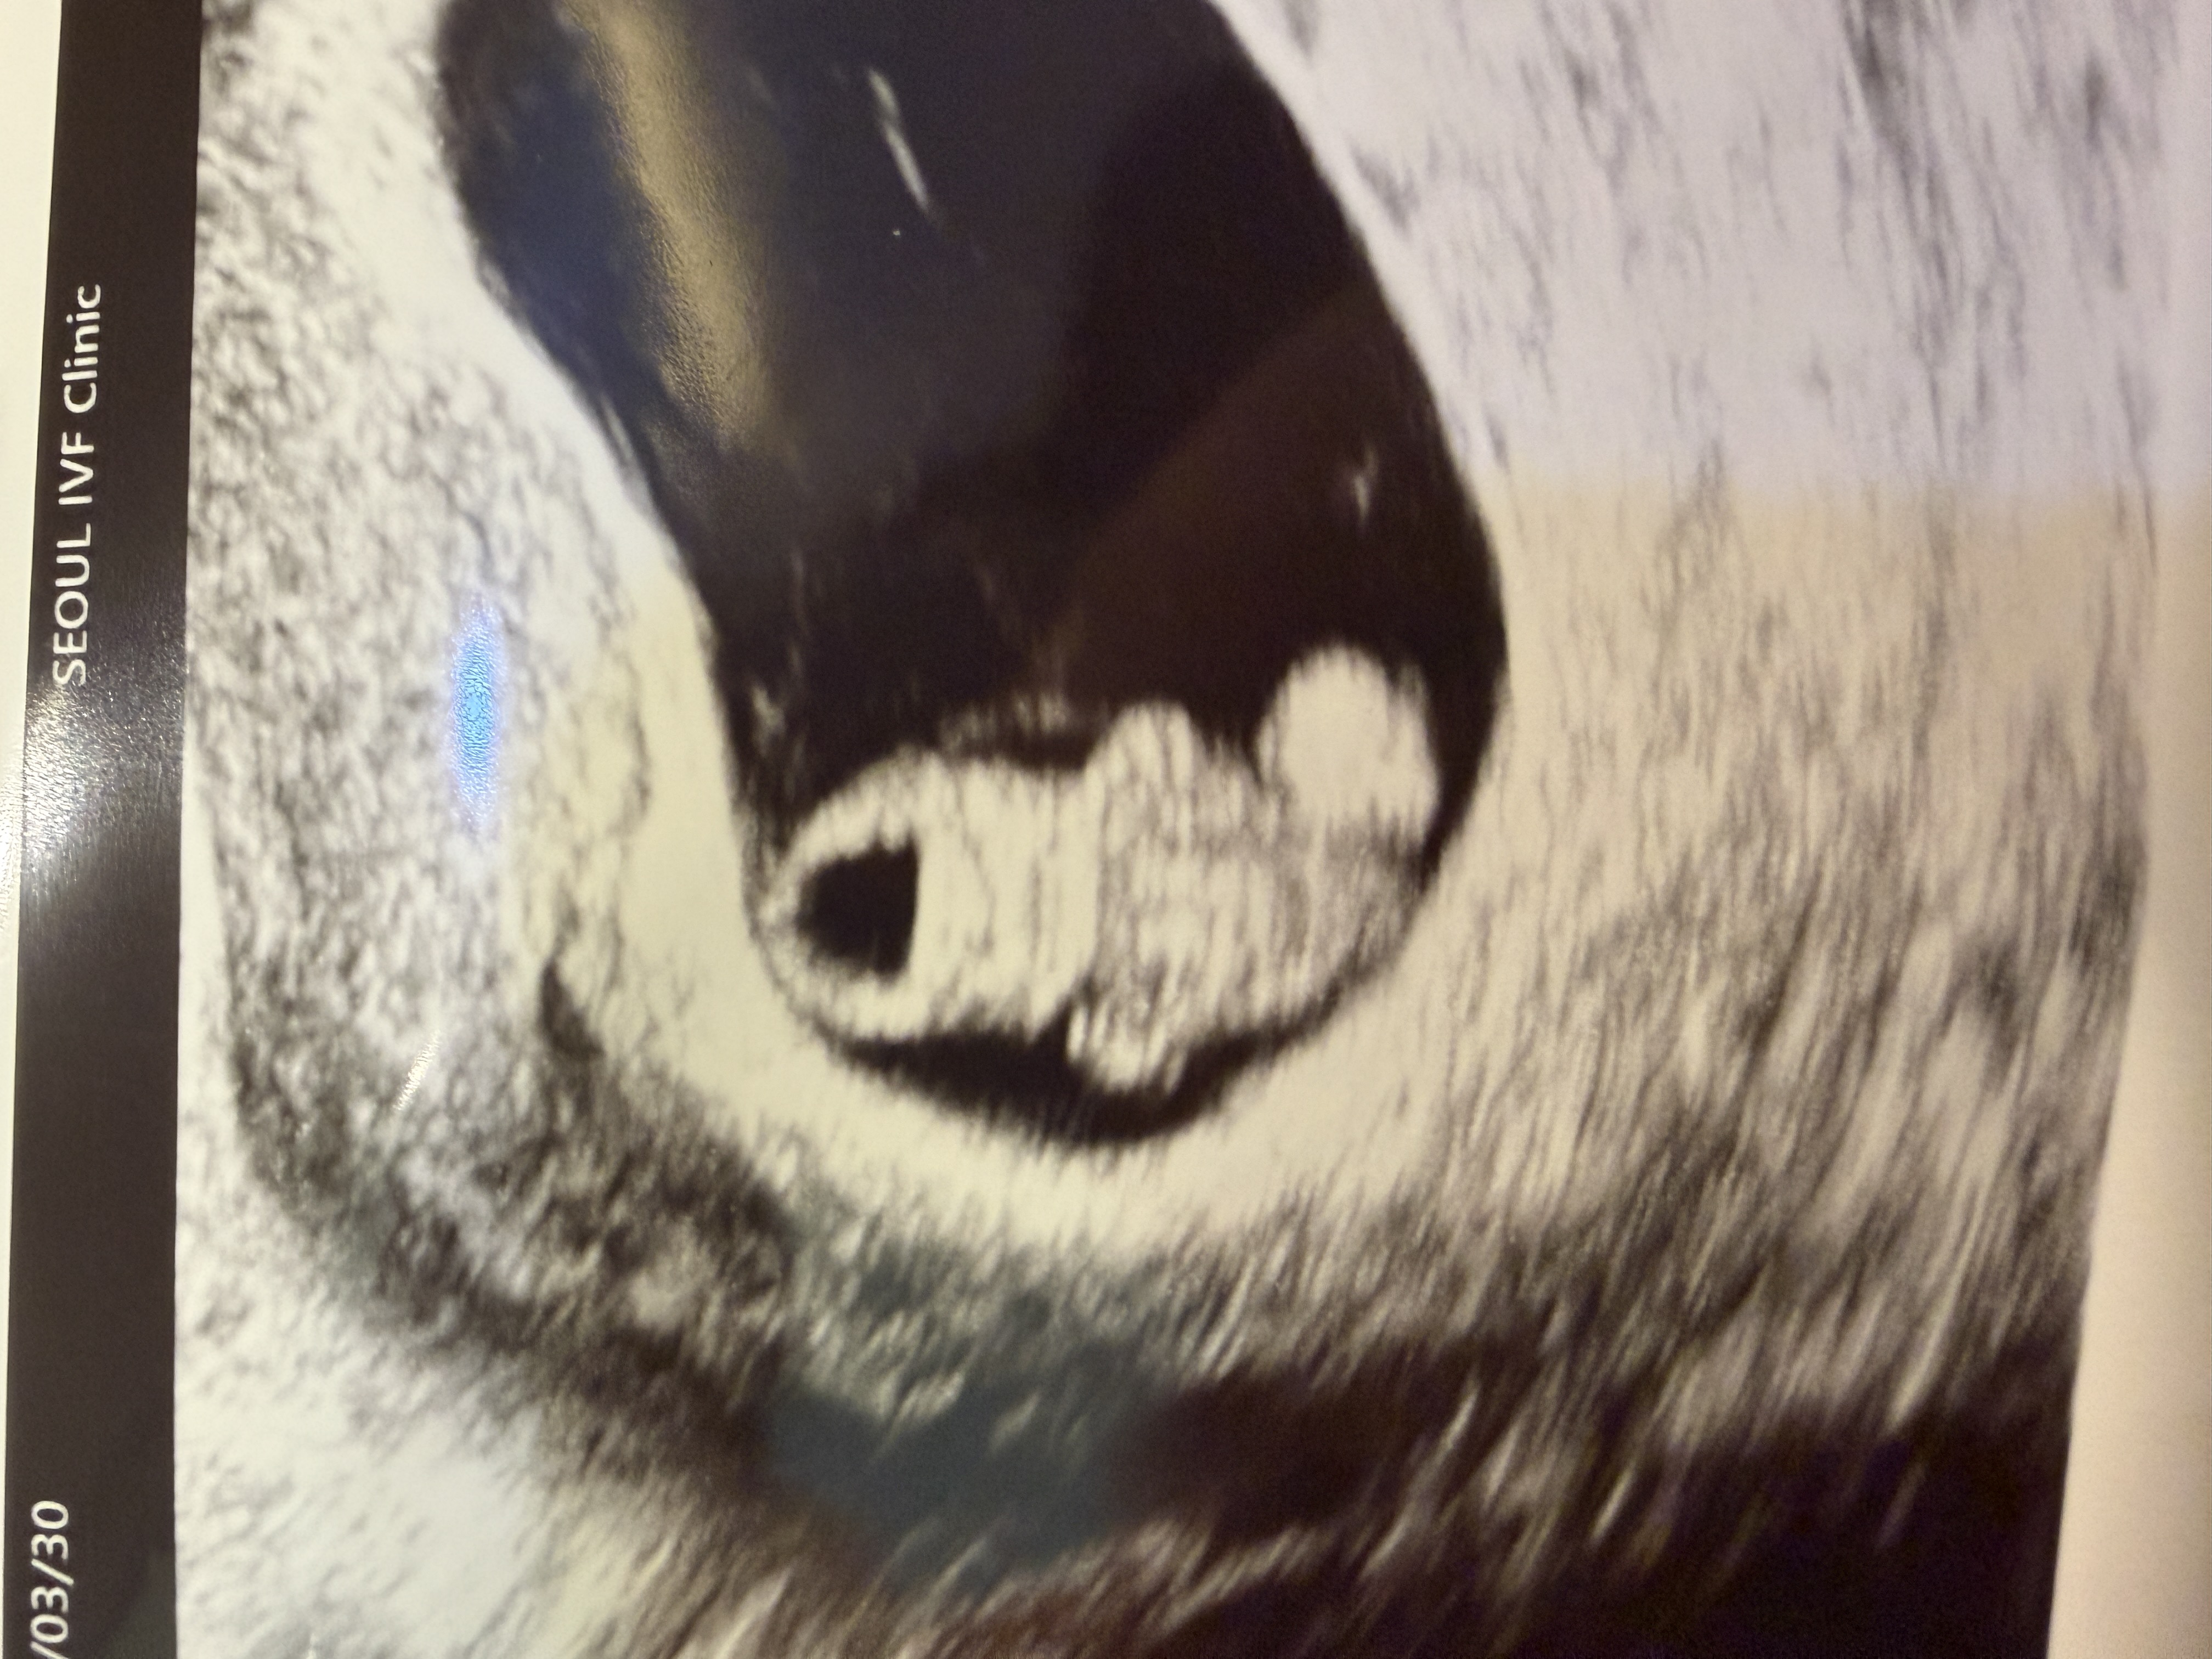

| 가슴 떨리는 임신 이야기를 공유해 주세요. | 인공수정 3차, 시험관 신선 2차를 거쳐 동결 1차에서 임신에 성공하게 되었습니다. 임신테스트기에서 처음 두 줄을 확인했던 날은 지금까지도 잊을 수 없는 순간입니다. |